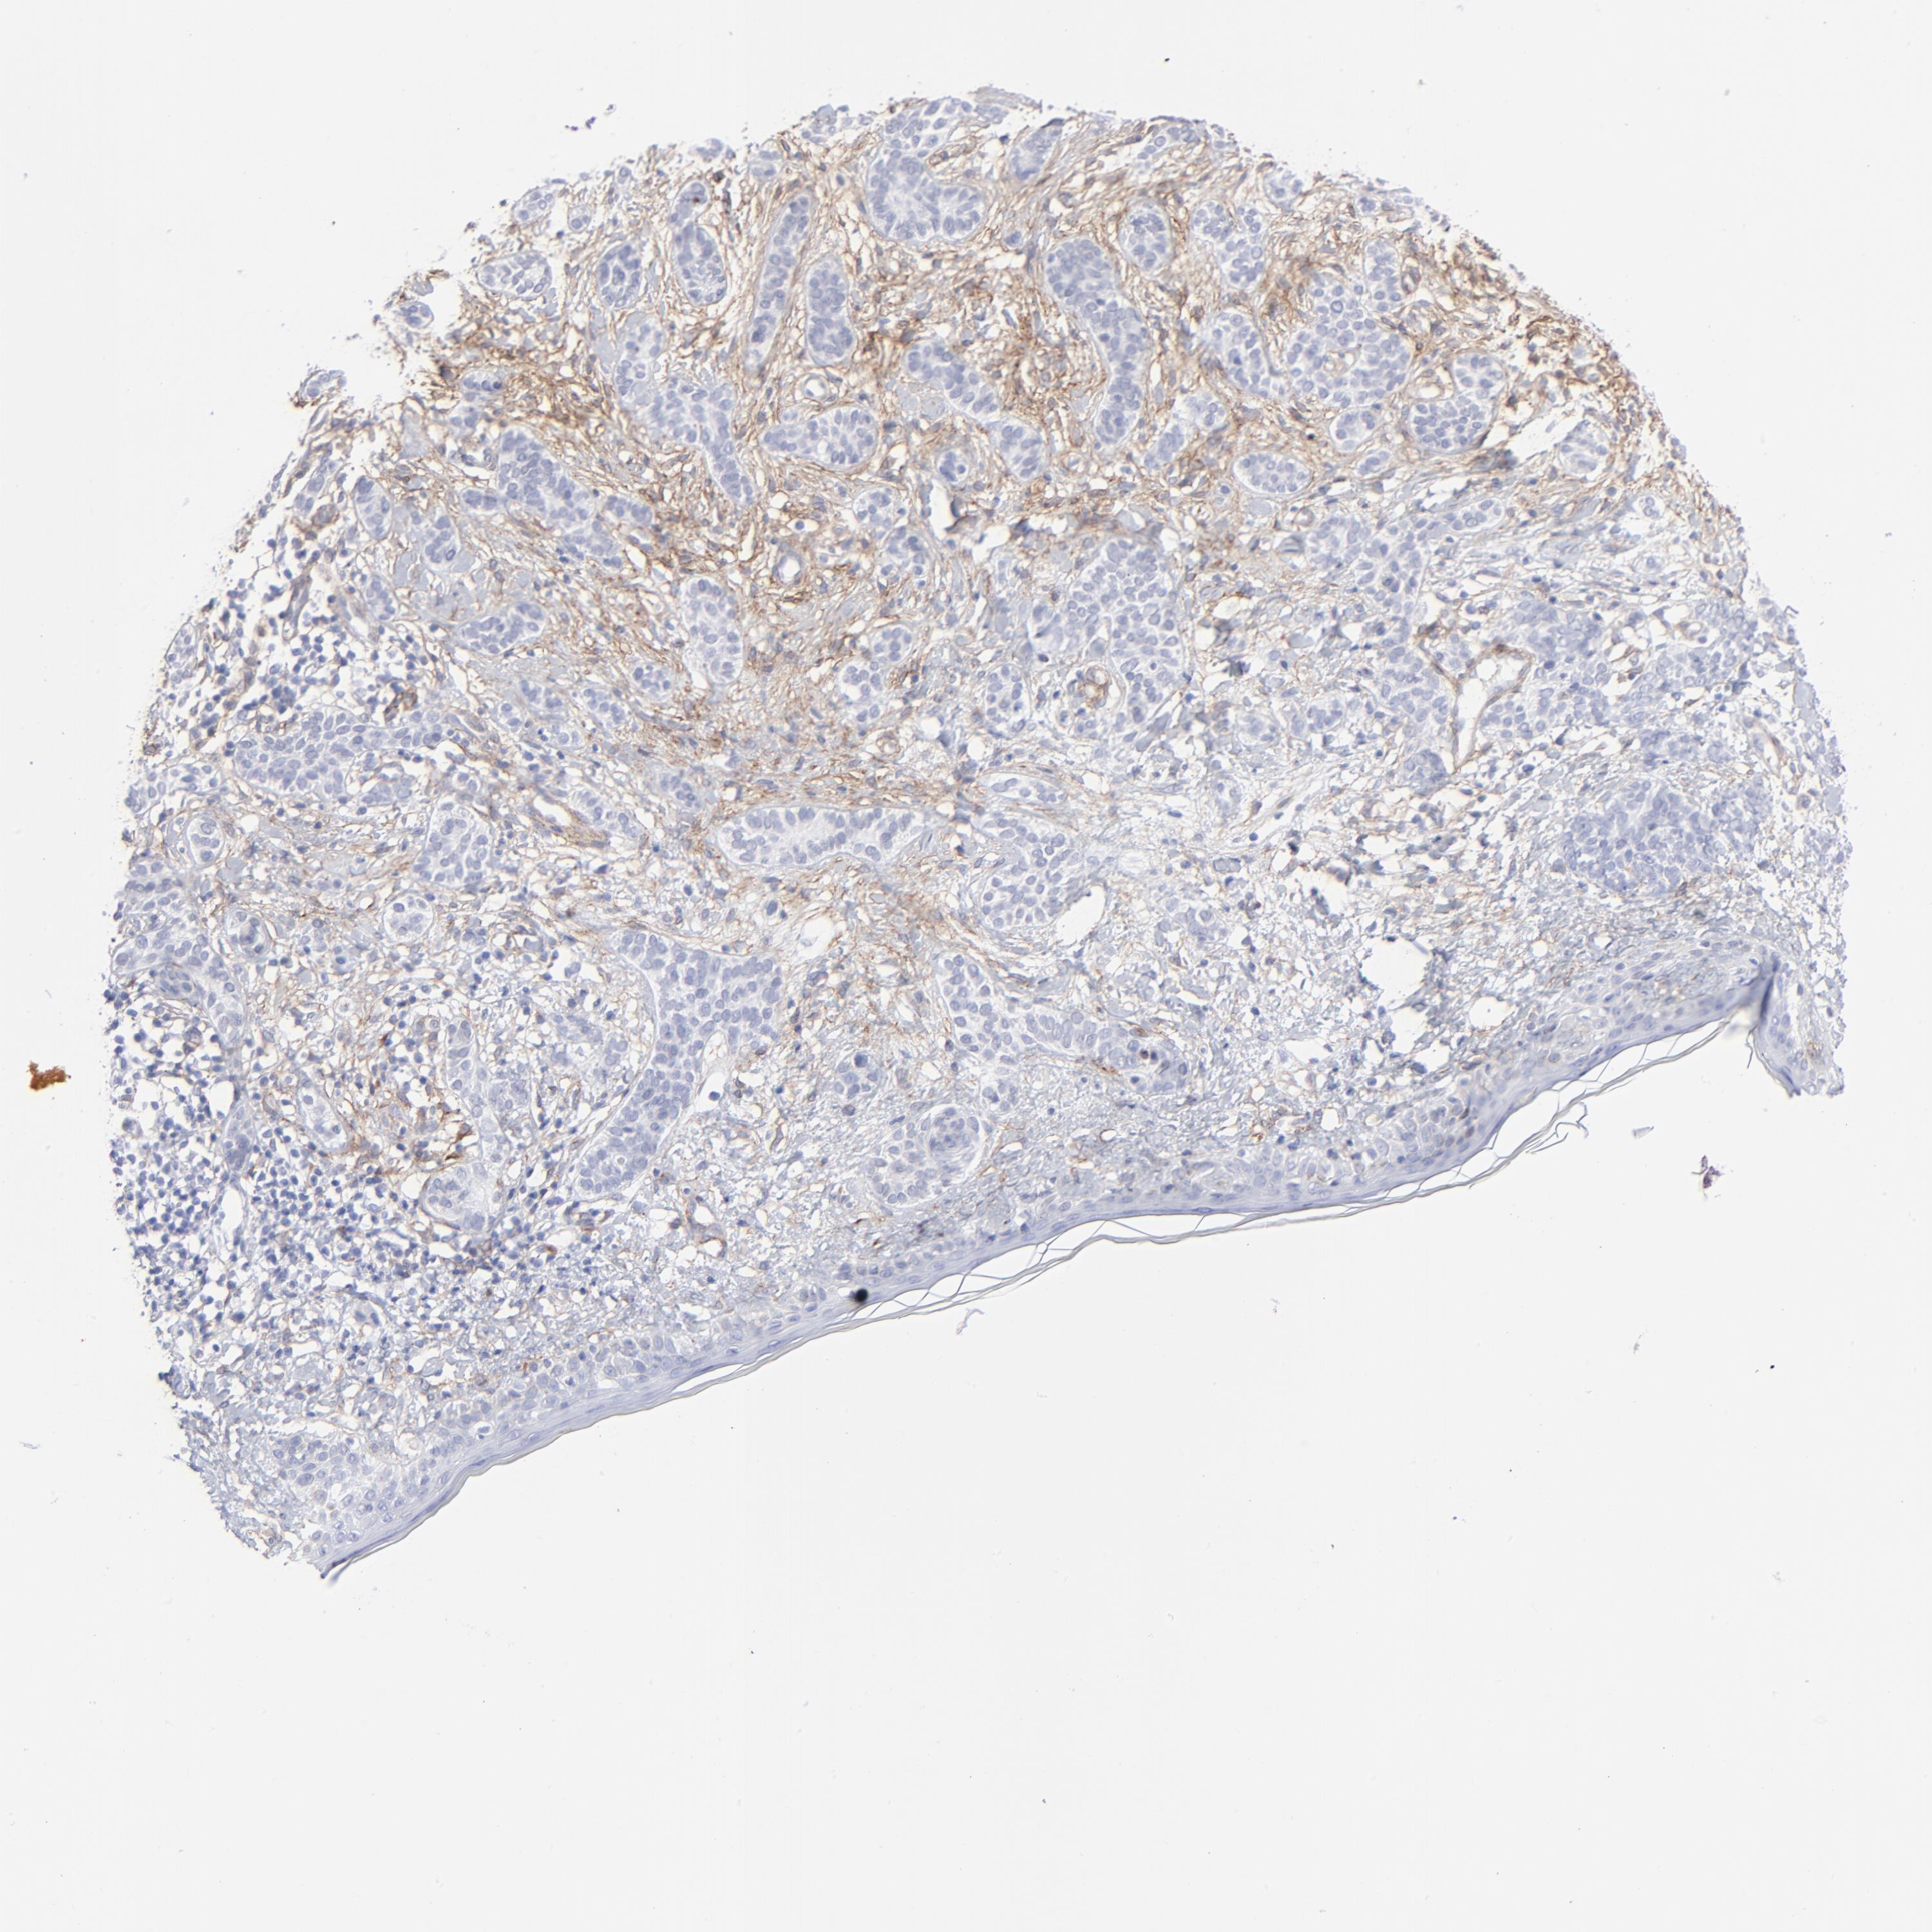

SKIN CANCER - Protein expressioni

A mouse-over function shows sample information and annotation data. Click on an image to view it in a full screen mode. Samples can be filtered based on level of antibody staining by selecting one or several of the following categories: high, medium, low and not detected. The assay and annotation is described here.

Antibody stainingi

Antibody staining in the annotated cell types in the current human tissue is reported as not detected, low, medium, or high, based on conventional immunohistochemistry profiling in selected tissues. This score is based on the combination of the staining intensity and fraction of stained cells.

Each image is clickable and will lead to virtual microscopy that enables deeper exploration of all samples and also displays staining intensity scores, fraction scores and subcellular localization as well as patient and tissue information for each sample.

Antibody CAB003842

Antibody CAB018144

Squamous cell carcinoma, NOS

Basal cell carcinoma

Squamous cell carcinoma in situ, NOS

Squamous cell carcinoma, metastatic, NOS